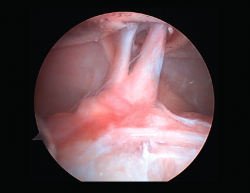

Rigidez

Una de las complicaciones más temidas, producida por un aumento del tejido fibroso, ya sea por la propia lesión (primaria) o secundaria a diferentes motivos (error técnico en la cirugía, síndrome del cíclope, inmovilización prolongada o la participación insuficiente en un programa de rehabilitación, infección, síndrome del dolor regional complejo, hematomas o sinovitis) (Figuras 7 y 8). Esta puede variar desde una ligera limitación del rango de movilidad hasta una severa artrofibrosis(21).

Figura 7. Adherencias intraarticulares.

Las principales causas secundarias a errores técnicos son la malposición de la plastia y el tensado excesivo. La radiografía permite ver la localización de los túneles e implantes, así como la RM visualiza las partes blandas implicadas, pudiendo identificar posibles pinzamientos de la plastia –escotadura intercondílea, síndrome del cíclope (Figura 9), síndrome de la contractura infrapatelar(22)(Figura 10)–.

Figura 9. Cíclope, tejido fibroso interpuesto en la cara anterior de la plastia y que produce pinzamiento de la misma en extensión de rodilla.